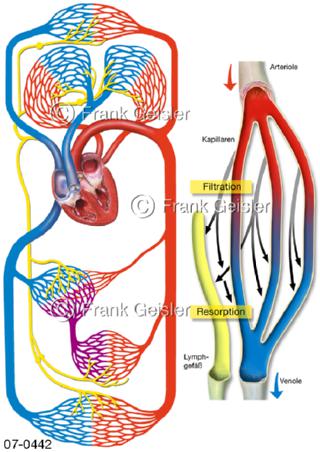

Bilder zu Herz, ein muskuläres Hohlorgan, das den menschlichen Körper durch rhythmische Kontraktionen mit Blut versorgt und dadurch die Durchblutung der Organe sichert, das Kreislaufsystem zeigt den Transport von arteriellem sowie venösem Blut durch das kardiovaskuläre System (Herz-Kreislauf-System), bestehend aus Blutgefäßen, Lymphgefäßen und dem Herz